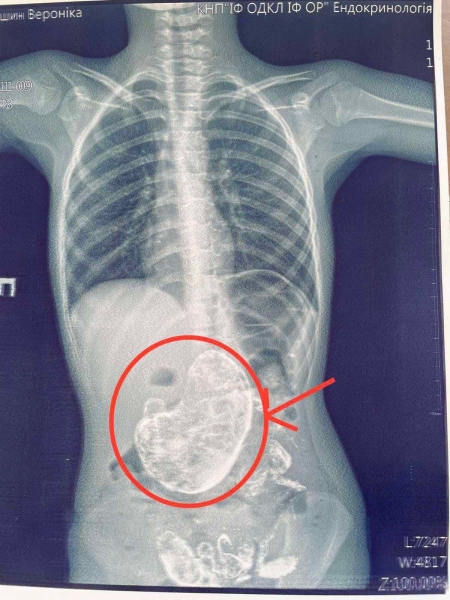

«Це трапляється частіше, ніж ви могли б подумати: 6-річна Вероніка потрапила в ОДКЛ зі скаргами на відмову від їжі, інших насторожуючих симптомів не було, результати аналізів були в нормі. Амбулаторне лікування не дало позитивного ефекту, тому дівчинку було госпіталізовано в гастроентерологічне відділення. Rtg дослідження шлунково-кишкового тракту допомогло виявити стороннє тіло в шлунку, а ФЕГДС підтвердила наявність тріхобезоару. Завдяки злагодженій роботі команди гастроентерологів, анестезіологів і хірургів пацієнтку було успішно прооперовано, і стороннє тіло сформоване з волосся (вагою 1 кг!) видалено. Так що пильнуйте, щоб ваші діти не їли волосся, бо наслідки можуть бути такими», — написав він.